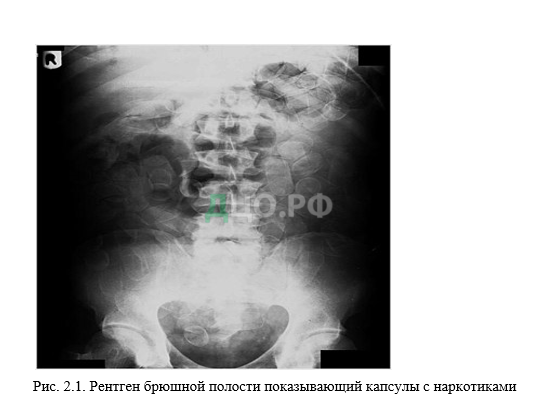

Это часто делается с использованием желудочно-кишечного тракта курьера или других полостей тела в качестве контейнеров. Глотание используется для перевозки героина, кокаина, и МДМА или экстази (рис.2.1.).

Обычное обнаружение контрабандных пакетов чрезвычайно сложно, и многие случаи выявляются из-за разрыва пакета или из-за кишечной непроходимости. Неразорванные пакеты иногда могут быть обнаружены при ректальном или вагинальном исследовании, но единственным надежным способом является рентгенография брюшной полости.